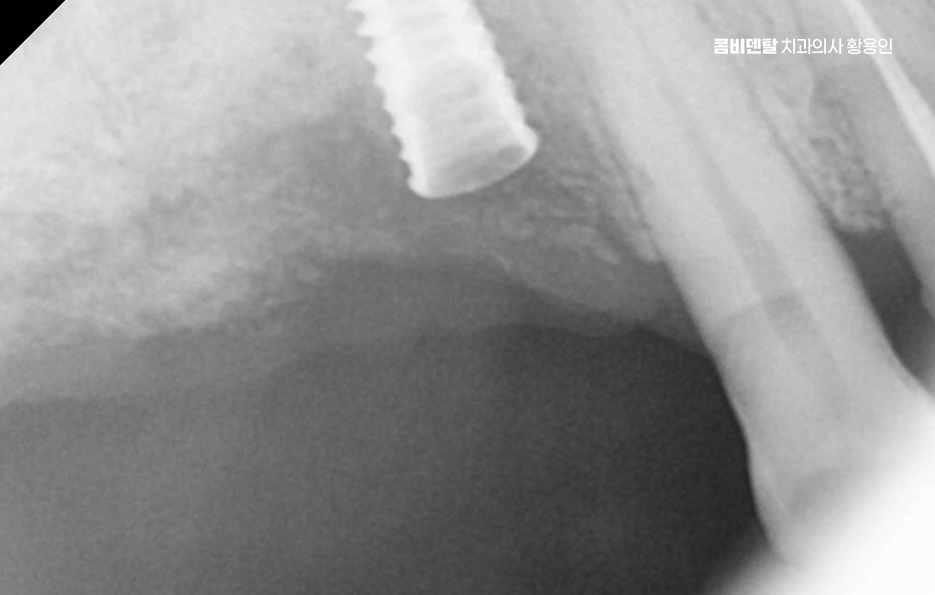

어금니 임플란트 과정은 정밀 진단에서 시작되며 잇몸뼈 안에 인공 치근을 심는 방식이기 때문에 뼈 상태 확인이 필수적으로 파노라마 촬영이나 3차원 CT를 통해 뼈 높이와 폭, 신경 위치를 확인하고 특히 아래 어금니는 하치조신경과 가까워서 정확한 위치 파악이 중요하며 위 어금니는 상악동과의 거리도 고려해야 할 필요가 있어요

임플란트를 심을 잇몸 뼈가 충분하다면 바로 식립이 가능하지만 치아를 빼고 오래 방치한 경우에는 뼈가 흡수되어 부족할 수 있으며 이때는 뼈이식을 먼저 하거나 동시에 진행하고 어금니는 씹는 힘이 강하기 때문에 초기 고정이 단단해야 하며 유지까지 고려할 때 교합의 정교한 맞물림이 중요한 부위라고 할 수 있었어요